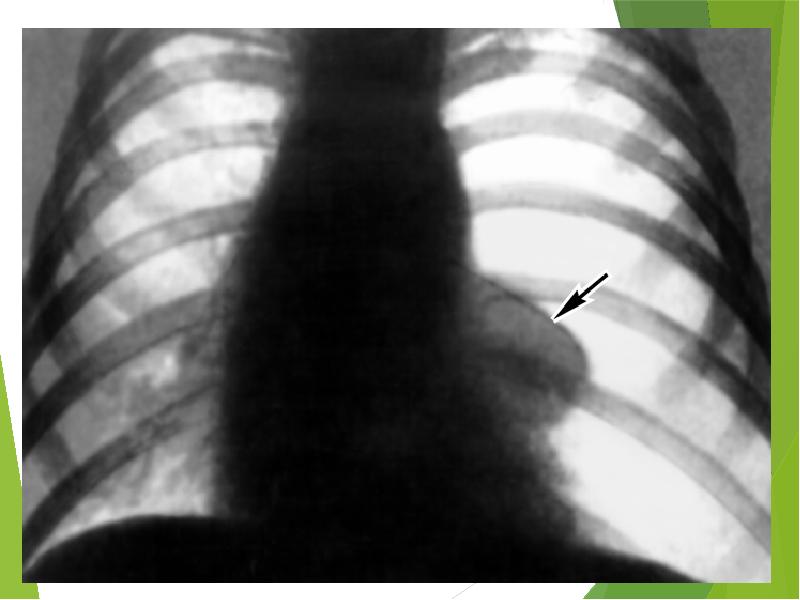

- 20. Специфические лабораторные изменения при пневмотораксе не определяются. Окончательное подтверждение диагноза происходит